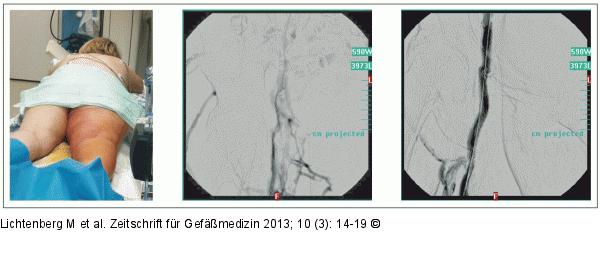

Abbildung 2: Rotationsthrombektomie Patientin mit Phlegmasie der rechten unteren Extremität. Rotationsthrombektomie mit dem Aspirex®-8-F-Katheter transpopliteal mit funktionell guten Abflussverhältnissen venös nach Thrombektomie. |

Patientin mit Phlegmasie der rechten unteren Extremität. Rotationsthrombektomie mit dem Aspirex®-8-F-Katheter transpopliteal mit funktionell guten Abflussverhältnissen venös nach Thrombektomie. |